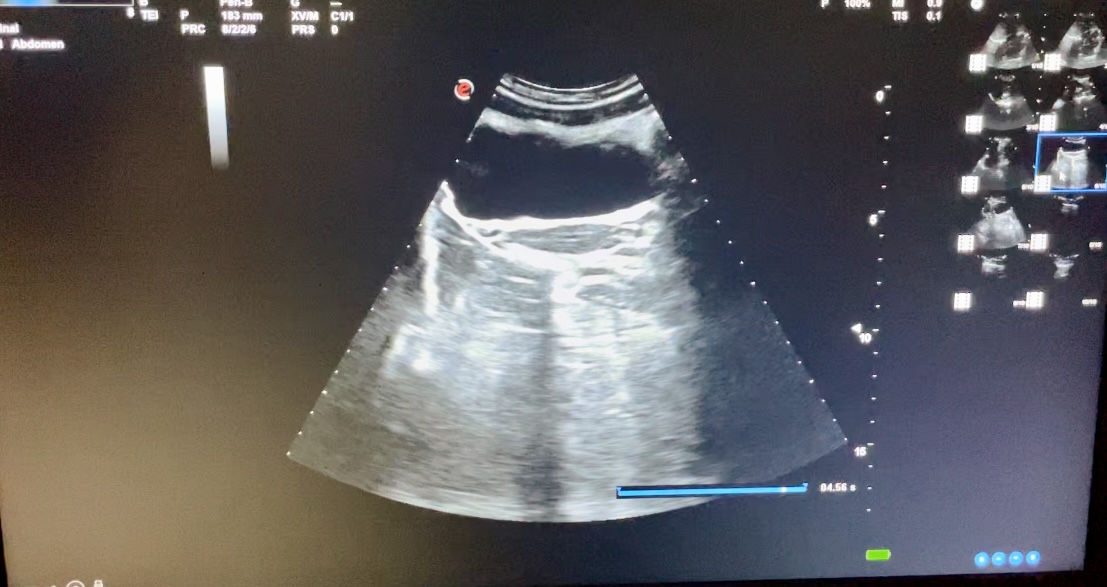

Estudio ecográfico con sonda abdominal de baja frecuencia, siguiendo protocolo ECO-FAST. Se explora región subxifoidea sin apreciarse presencia de líquido en saco pericárdico. Hipocondrio derecho libre de líquido en espacio de Morrison. Hipocondrio izquierdo sin presencia de líquido en espacio esplenorrenal. Imagen de región supra púbica, corte longitudinal y transversal donde no se observa líquido libre en saco de Douglas.